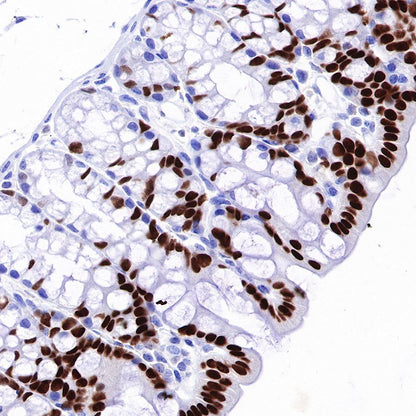

Immunohistochemistry

IHC shows positive staining in paraffin-embedded human colon. Anti-HNF4α antibody was used at 1/500 dilution, followed by a HRP Polymer for Mouse & Rabbit IgG (ready to use). Counterstained with hematoxylin. Heat mediated antigen retrieval with Tris/EDTA buffer pH9.0 was performed before commencing with IHC staining protocol.

IHC shows positive staining in paraffin-embedded mouse colon. Anti-HNF4α antibody was used at 1/500 dilution, followed by a HRP Polymer for Mouse & Rabbit IgG (ready to use). Counterstained with hematoxylin. Heat mediated antigen retrieval with Tris/EDTA buffer pH9.0 was performed before commencing with IHC staining protocol.